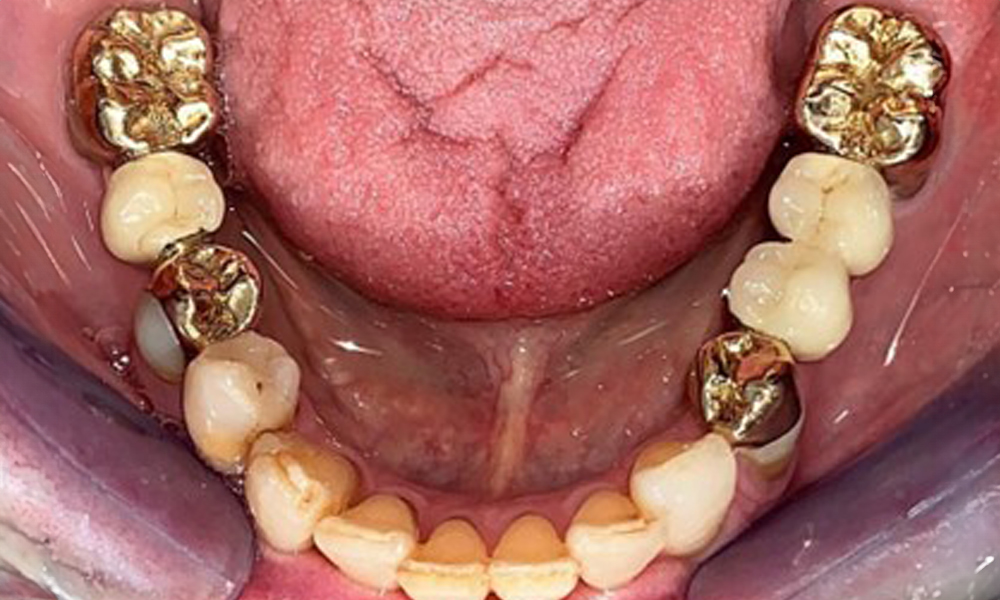

The patient was fitted with a combined removable maxillary telescopic prosthesis more than 25 years ago (Fig. 1, Fig. 2, Fig. 3) and is very happy with her dentures. The patient has an adequate fixed denture for the mandible (Fig. 4).

The dental findings are as follows: Combined removable implant and tooth-supported telescopic prostheses on implants 15, 13, 21, 23, 24, 25 and tooth 11 (Fig. 1, Fig. 2, Fig. 3). The patient was fitted with a fixed mandibular denture. Adequate bridges were present over 37 to 34 and 45 to 47 (Fig. 4), the crown margins were intact and there were no active caries. A composite filling with a marginal gap was present on tooth 43. There was mandibular gingival recession, exposing 1 to 3 mm of root surface. This also applies to 11.

The radiological findings show partially edentulous dentition with maxillary implants for teeth 15, 13, 21, 23, 24, 25 and a telescopic crown on tooth 11. Adequate mandibular bridges spanning 37 to 34 and 45 to 47 are present. 48 is impacted. There are suspected secondary caries distally on 43 and mesially on 44. 44 is restored with a non-radiopaque cavity lining. There is generalised horizontal bone loss of approx. 10% to 30% and localised vertical bone loss affecting teeth 22 and 42 (Fig. 5).